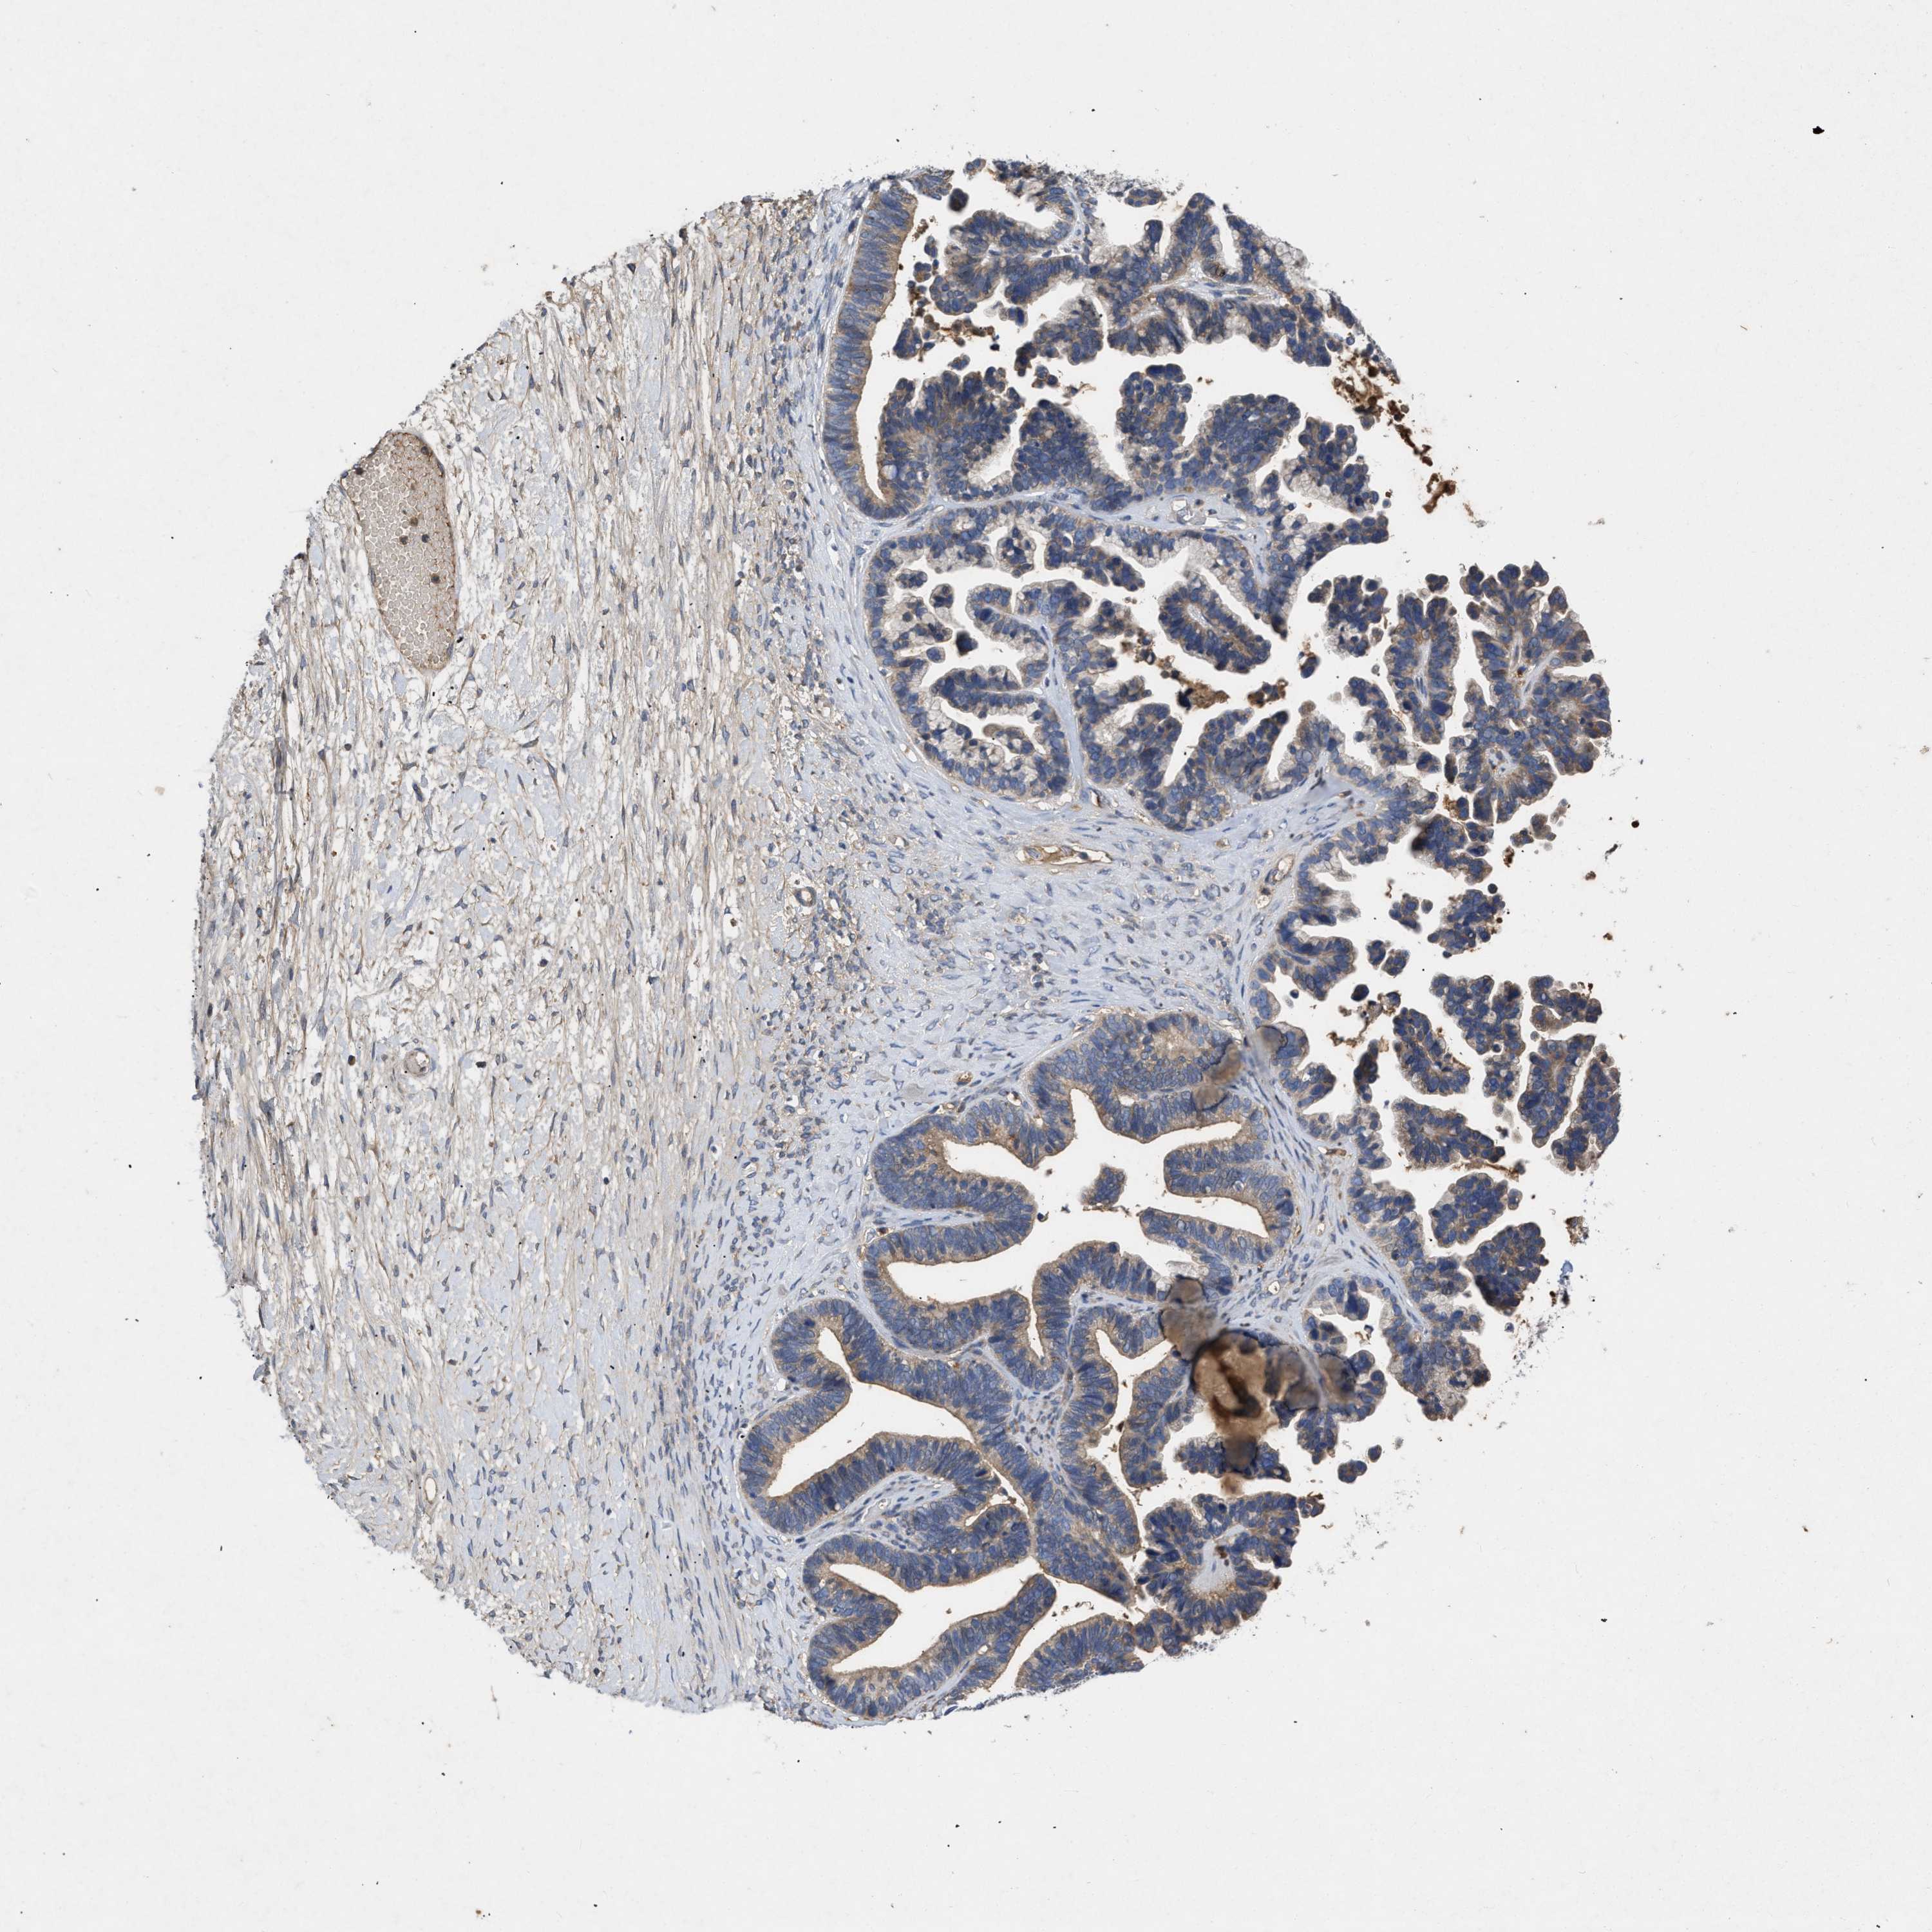

OVARIAN CANCER - Protein expressioni

A mouse-over function shows sample information and annotation data. Click on an image to view it in a full screen mode. Samples can be filtered based on level of antibody staining by selecting one or several of the following categories: high, medium, low and not detected. The assay and annotation is described here.

Note that samples used for immunohistochemistry by the Human Protein Atlas do not correspond to samples in the TCGA dataset.

Antibody stainingi

Antibody staining in the annotated cell types in the current human tissue is reported as not detected, low, medium, or high, based on conventional immunohistochemistry profiling in selected tissues. This score is based on the combination of the staining intensity and fraction of stained cells.

Each image is clickable and will lead to virtual microscopy that enables deeper exploration of all samples and also displays staining intensity scores, fraction scores and subcellular localization as well as patient and tissue information for each sample.

Antibody CAB018751

Antibody CAB034411

Cystadenocarcinoma, serous, NOS

Carcinoma, endometroid

Cystadenocarcinoma, mucinous, NOS

Carcinoma, NOS